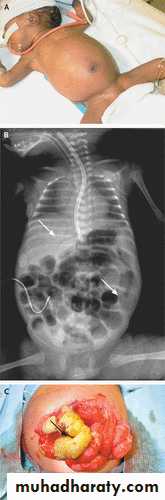

This is a radiograph of a 1-day-old infant with a moderate-sized

congenital diaphragmatic hernia. Note the air- and fluid-filled bowel loopsin the left chest, the moderate shift of the mediastinum into the right chest,

Isolated esophageal atresia (EA). . Note the absence of bowel gas in this patient with EA

,